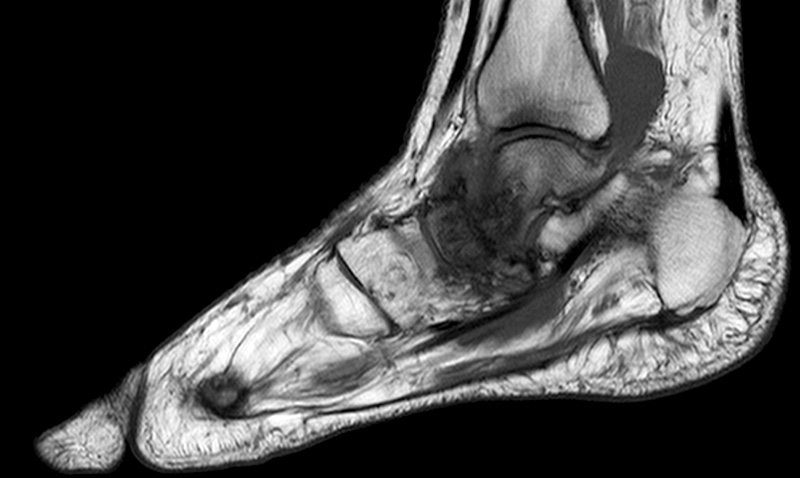

I motsats till slätröntgen har magnetresonanstomografi (MRT) hög sensitivitet och specificitet även i den tidiga fasen, och normalt fynd vid MRT talar starkt emot Charcotfot [25]. På MRT ses i den tidiga fasen benmärgsödem i de drabbade benen. MRT kan dessutom vanligen, men inte alltid, särskilja Charcotfot från osteomyelit, då förändringarna vid Charcotfot i regel har en periartikulär utbredning [28]. Då MRT i regel inte görs akut måste initiala beslut baseras enbart på klinisk misstanke.

MRT av samma fot som i bilden ovan med benmärgsödem i caput tali och os naviculare.